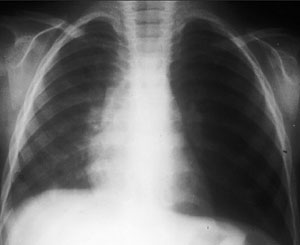

Radiología: La radiografía de tórax es útil pero no imprescindible si no existe duda diagnóstica. El signo más constante es la hiperinsuflación. También pueden observarse engrosamiento peri bronquial, infiltrados peris hiliares bilaterales, áreas de consolidación parenquimatosa en parches, atelectasias segmentarias o subsegmentarias.

Hiperinsuflación del pulmón izquierdo por atrapamiento aéreo